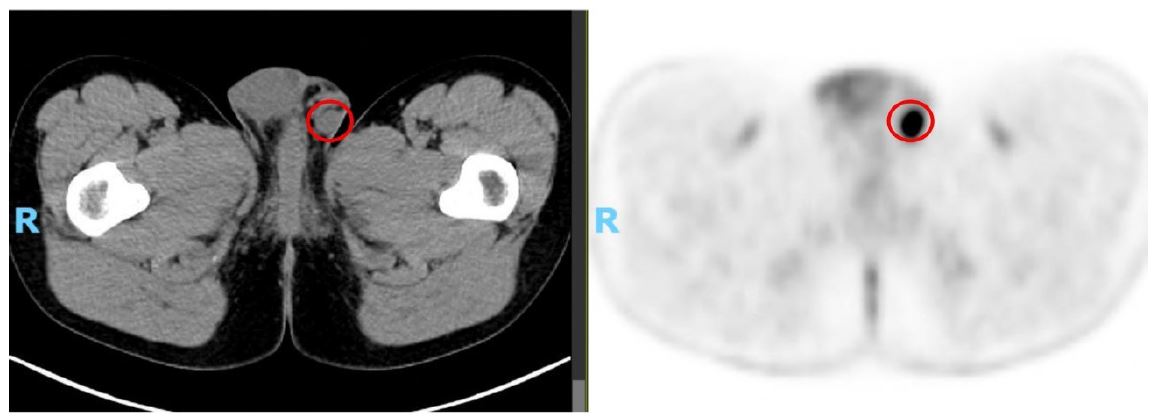

At the first reassessment after four cycles of selpercatinib, a response was observed, marked by a significant reduction in tumor mass and disease stability confirmed by subsequent imaging (Figures 4 & 5).

Figure 5: The left image depicts the testicular lesion at diagnosis (May 2023), while the right image illustrates its resolution following 13 cycles of selpercatinib (January 2025).